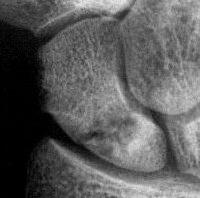

1. Nondisplaced fracture in a surgeon who declined continuous immobilization.

One week after screw stabilization using a limited dorsal approach, he was back operating, but splinted when not scrubbed. These films are one month post op: no visible fracture.